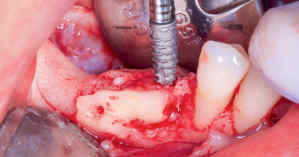

Etapa 2 – Reconstrução Óssea com Técnica de Khoury

Após a maturação do tecido gengival, procedeu-se ao preparo do leito receptor com incisão e descolamento mucoperiosteal,

liberando-se o tecido lingual por meio do alívio da tensão muscular do milo-hióideo (Fig. 3) com o descolador de Molt (Supremo Instrumentais). Em seguida, prosseguiu-se com a coleta de osso autógeno do ramo mandibular (área próxima ao leito receptor do mesmo lado) (Fig. 4). As lâminas ósseas foram adaptadas e fixadas nas corticais vestibular e lingual com parafusos de titânio (Orth – Implacil Osstem) (Fig. 5), criando um compartimento do tipo caixa, preenchendo-se o seu interior com osso particulado autógeno (Fig. 6). A sutura foi realizada com pontos em colchoeiro horizontal seguidos de pontos simples interrompidos (Fig. 7). A cicatrização foi considerada satisfatória.

Figura 3: Retalho, descolamento mucoperiosteal e liberação de tecido até ultrapassar o plano oclusal dos dentes adjacentes.

Figura 4: Coleta de bloco autógeno da região do ramo mandibular e preparo das lâminas por meio de cortes longitudinais com discos (American Burrs).

Figura 5: Fixação das lâminas com técnica compressiva e parafusos Orth (Implacil Osstem)

Figura 6: Preenchimento do “túnel” com osso autógeno particulado.

Figura 7: Suturas com fio de PTFE (Microsuture) em colchoeiro horizontal e em pontos simples interrompidos